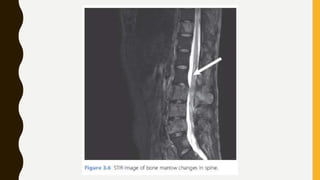

STIR Images

• STIR (Short TI Inversion Recovery) images, especially for spine and for musculoskeletal

imaging. STIR images have very low signal from fat but still have high signal from

fluids, i.e. they can be thought of as a ‘fat-suppressed T2w’ imaging technique.

however, bear in mind that STIR images will suppress all tissues with the same T1 as

fat, so they should not be used after gadolinium contrast injection when there may be

T1 changes in the pathology as well as in normal tissues.

• STIR is a type of IR sequence, like FLAIR, except that we choose to null fat-containing

tissues instead of CSF.